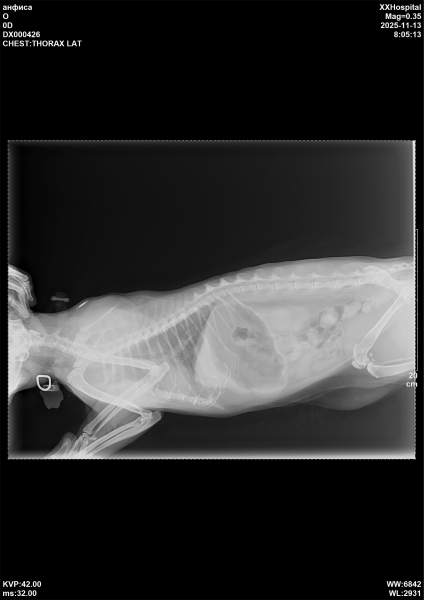

13.11.25 Фиса бронхопневмония

Сейчас обострение, развилась бронхопневмония.

Сдали биохимию и ОАК. По ОАК воспаление. Сделали рентген- в 2 часа ночи и в 8 утра

Бронхопневмония и заложенность носика сильная.

Усиленный бронхиальный рисунок на рентгене